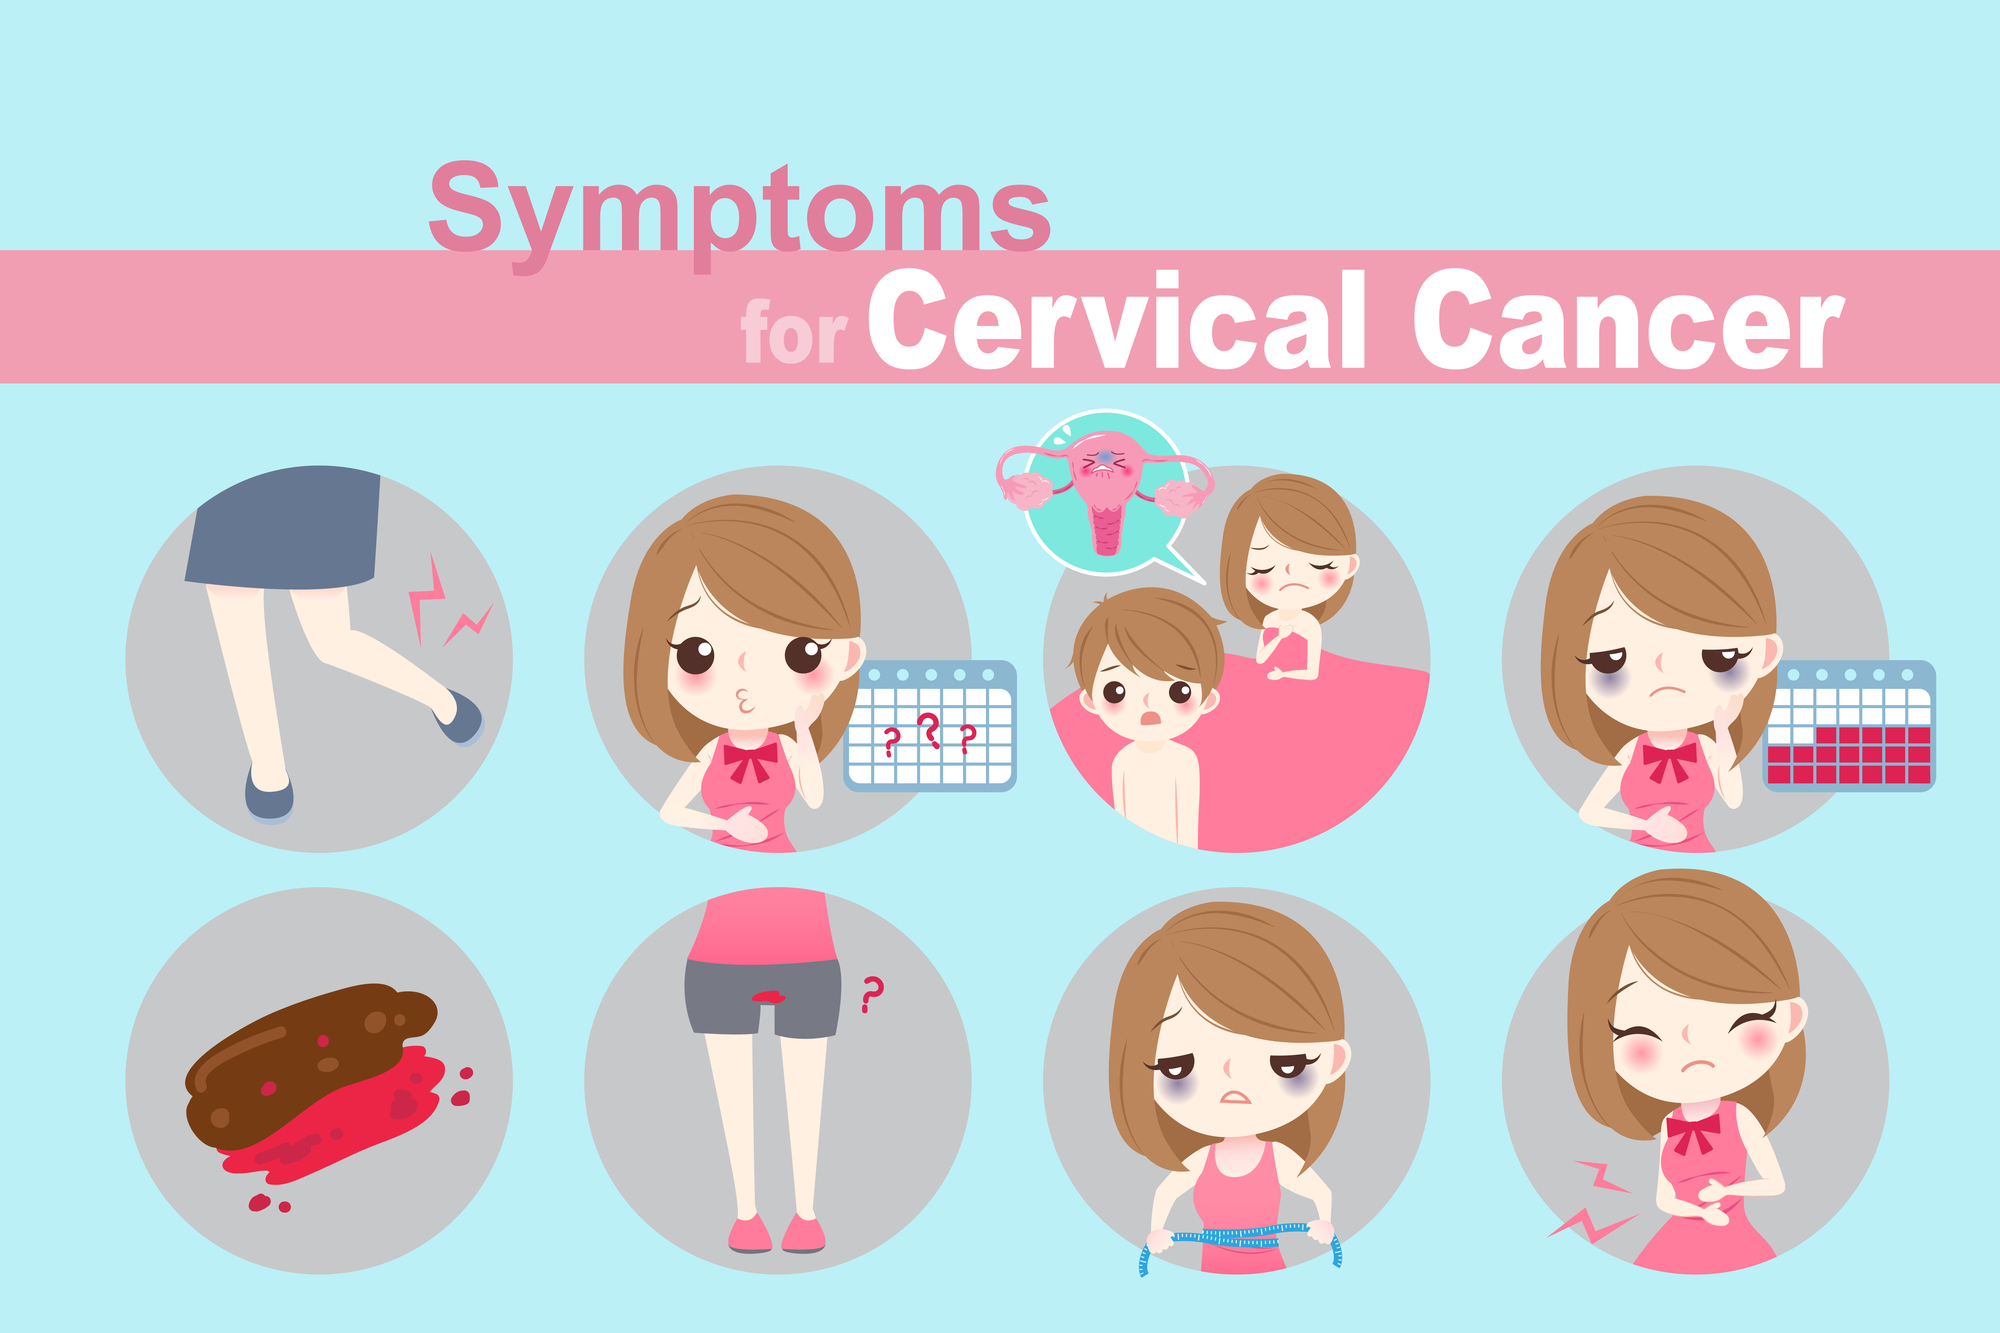

近年来,高龄女性生育需求持续增加。无论是因为晚婚晚育趋势,还是多次试管失败、卵巢功能下降等原因,许多 35 岁以上的女性在自然怀孕或试管婴儿治疗中都面临更大挑战。